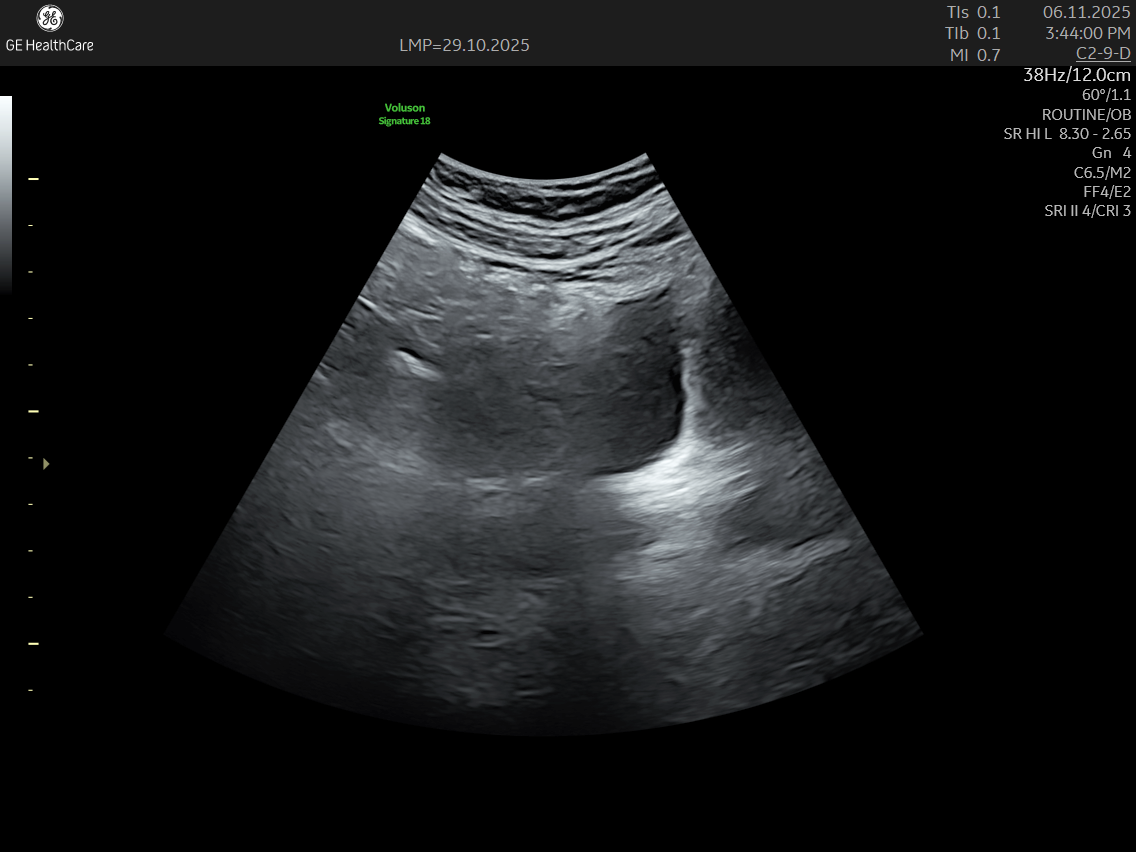

IMAGE GALLERY